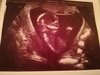

I już po wizycie [emoji2] jak widać dzidzia śliczna, duża i zdrowa. 7,41 cm [emoji7] [emoji7] [emoji7] w końcu mąż zobaczył ją na żywo i szczęśliwy jak nie wiem co [emoji1]

Ojjeeeeeeej, ale piękna!!!!! [emoji7][emoji7][emoji7][emoji7][emoji7][emoji7][emoji7]